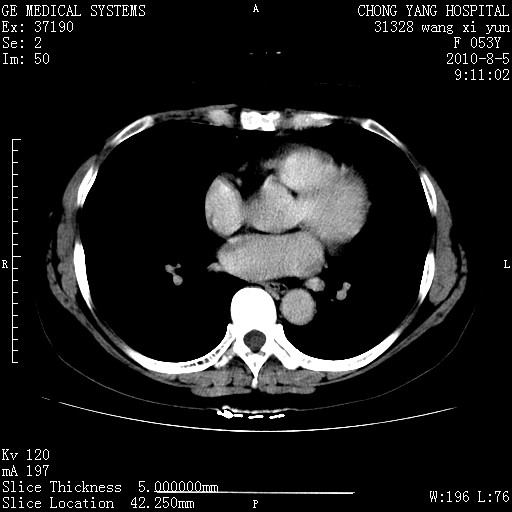

标题: CT28214:F41Y 血尿二十天,建议盆腔平扫加增强。

胆管细胞ca?

1)考虑肝左叶胆管细胞癌。2)脂肪肝。

支持胆管细胞ca。